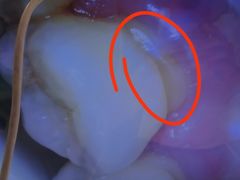

• 希望齿科(河西店)

• -希望齿科(河西店)